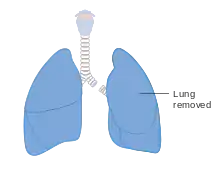

A pneumonectomy (or pneumectomy) is a surgical procedure to remove a lung. It was first successfully performed in 1933 by Dr. Evarts Graham. This is not to be confused with a lobectomy or segmentectomy, which only removes one part of the lung.

Living with one lung

As with the kidneys, it is often possible for a person to live with just one lung. Although it is not possible for the lung to re-grow like the liver, the body is able to compensate for the reduced lung capacity by slow and gradual expansion of the other remaining lung. Post-pneumonectomy patients in due time reach about 70–80 percent of their pre-surgery lung function.[10] People have been able to return to near-normal lives, including running marathons after a pneumonectomy, provided there has been adequate cardio-pulmonary conditioning.[11]